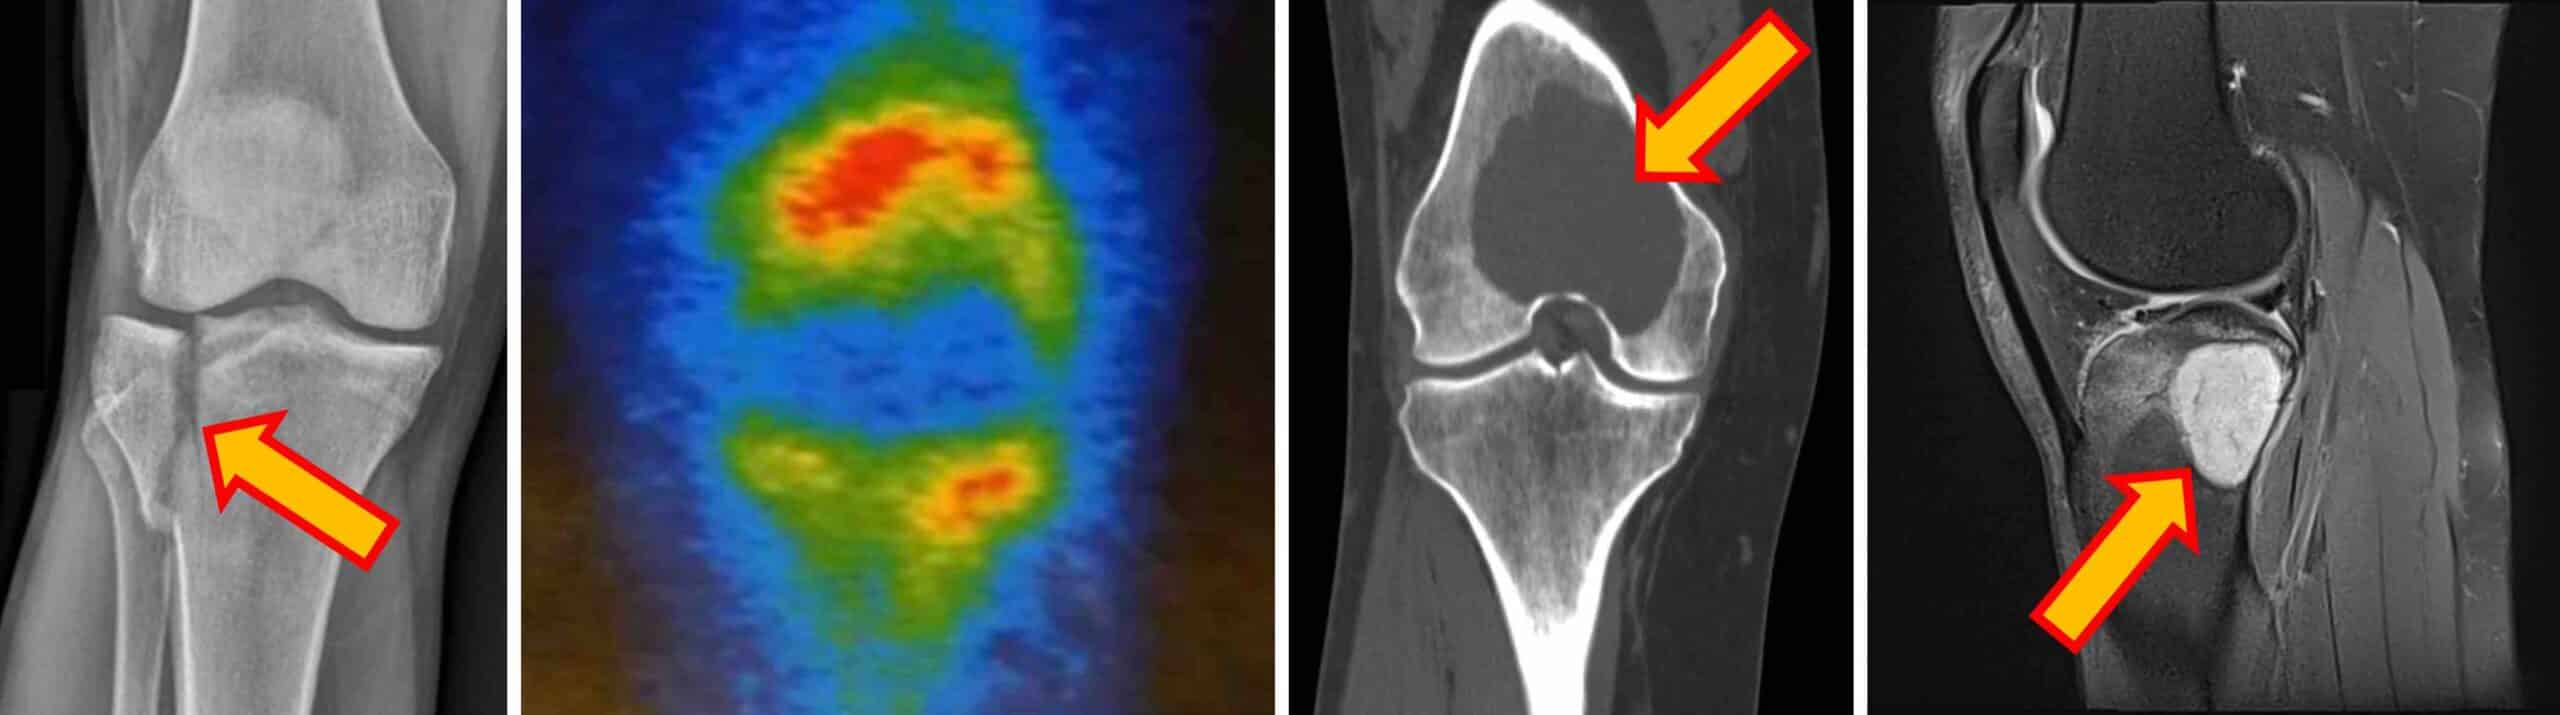

DIAGNÓSTICO

O diagnóstico de dor no joelho de origem óssea é feito pelo exame físico da articulação e por exames de imagem como RX, tomografia computadorizada, ressonância magnética e cintilografia óssea. Os exames de imagem identificam alterações ósseas, fraturas, tumores e degenerações articulares.